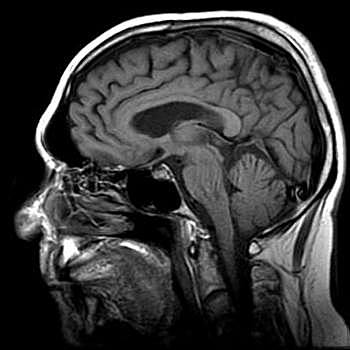

Cerebro base 400x400

1) Surgimiento de las imágenes cerebrales.

Durante la década de 1990 se fortalece la investigación con el empleo de imágenes no ya anatómicas sino funcionales, en particular la resonancia magnética funcional (fMRI, por sus siglas en inglés) y la tomografía por emisión de positrones (PET), que han permitido visualizar la actividad cerebral durante la realización de diferentes tareas cognoscitivas (por ejemplo, hablar, leer, pensar en palabras, etc.).